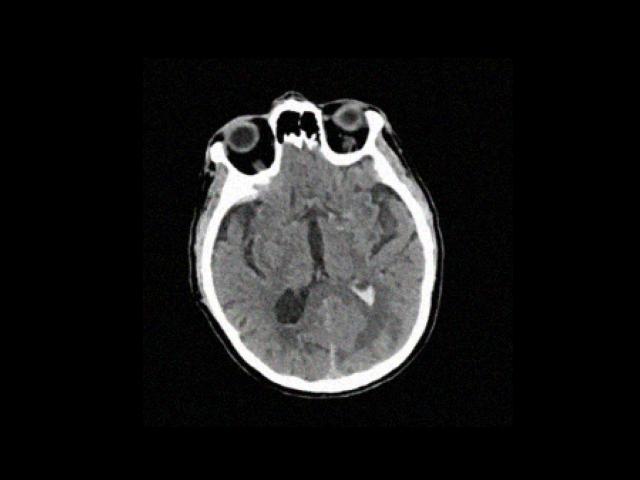

Sample Gallery